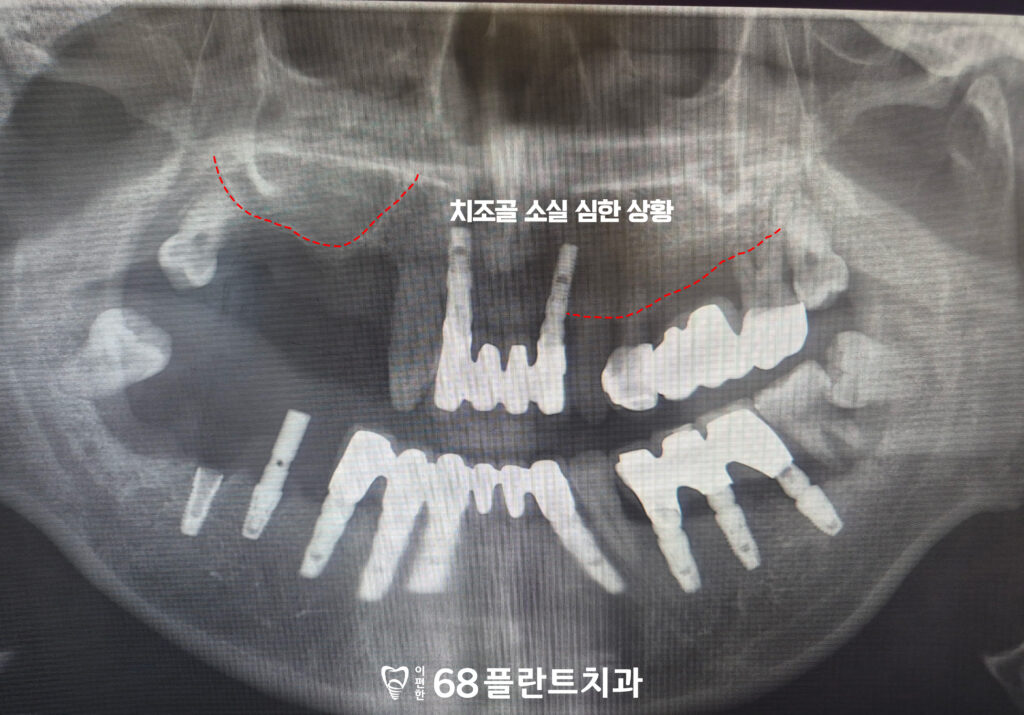

<치조골 소실 심한 상황>

위 환자분께서는

치아가 상실된 부위도 있고

있는 치아들도 흔들리고 불편하다며

본원에 내원해 주셨습니다.

확인해 보니,

오른쪽 위는 치아가 상실된 시간이 길어져

잇몸뼈까지 많이 소실되어 있었으며,

상악동과 거리가 가까워 임플란트를 식립하기에는

골 높이가 충분하지 않은 상태였습니다.

또한 남아 있는 치아들 역시 치주질환으로 인해

지지 조직이 약해져 동요도가 관찰되었고,

전반적인 구강 상태의 개선이

필요한 상황이었습니다.